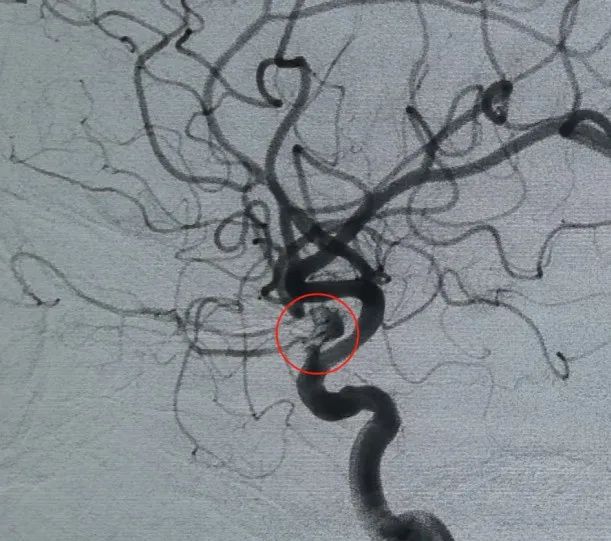

診断: 左内頸動脈C6セグメント眼動脈動脈瘤

血管アクセスは、大腿動脈穿刺とPerdenserを介して確立されました®6mm × 20 cmの3Dコイルが最初に配備されてバスケットを形成し、安定した壁の配置を実現し、安全な静脈内サポートを提供しました。 これに続いてPerdenserが挿入されました®6mm × 15 cmの3Dコイルで、葉状の娘嚢内の血流を妨害します。

パーフィラー®3mm × 6 cmの拡大可能なコイルおよびパーフィラー®次いで、3mm × 2 cmの拡張可能なコイルを配置して、首の咬合を完了させた。 その後、ヌバ®フローダイバーター (TJED-D-5.0-16) を投与し、動脈瘤の首全体に展開しました。 前後および横方向の両方のビューでの追跡血管造影により、優れたカバレッジ、良好な壁の配置、および明確な放射線不透明度が確認され、顕著なコントラストの停滞が確認されました。